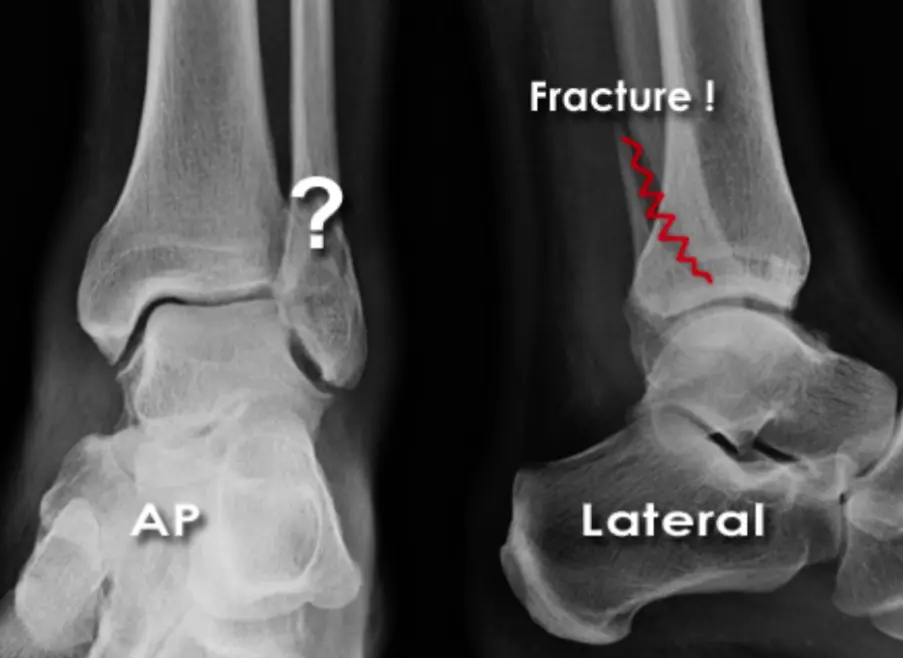

36âyearâold lady presents after a twisting ankle injury.

The ankle is swollen and tender, and she is unable to bear weight.

- Question: Is there a fracture?

- Likely site: possible lower fibula fracture

- Imaging needed: a lateral ankle film